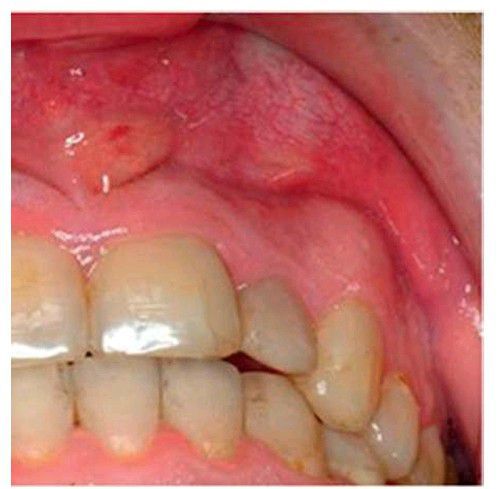

Vestibular space infection

Fluctuant edema and erythema of the maxillary left anterior vestibule associated with necrotic pulp of the maxillary left lateral incisor.